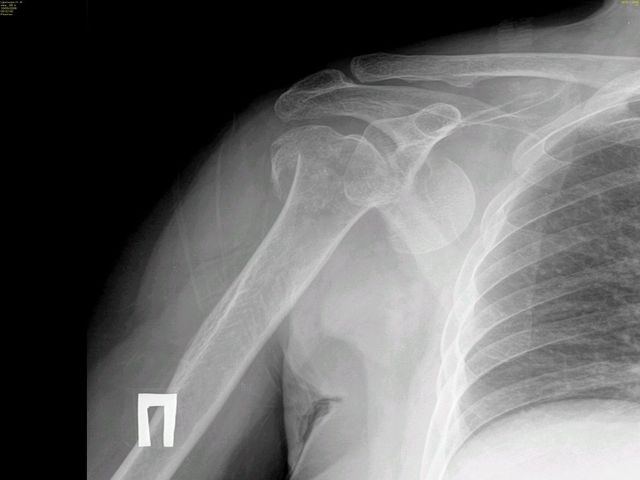

Re: несвежий переломо-вывих плеча

Не передаются фото, хотя все условия выполняются. Попробую еще раз. Простите.